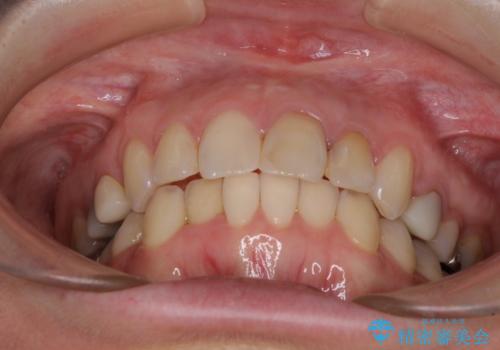

【モニター】前歯のデコボコと奥歯の虫歯 インビザライン治療と奥歯のセラミック治療

- 前歯のデコボコと奥歯の虫歯を気にして来院された患者様です。

主に下顎歯列全体の後方移動とIPR(歯と歯の間を削る)によってデコボコが解消するように設計し、インビザラインにより治療を行うこととしました。

矯正治療後半に下顎左右奥歯をセラミッククラウンにて補綴し、その後インビザラインによる歯列の仕上げを行うこととしました。

下顎前歯の叢生が速やかに改善されたため、1年3か月で治療を終えることができました。

下顎前歯は後戻りを起こしやすいため、舌側を細いワイヤーで固定することで後戻り対策を行っています。